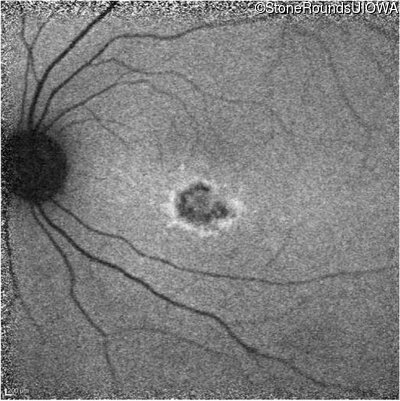

Infrared Fundus Photograph - Left - 20/25 -1

Exemplar